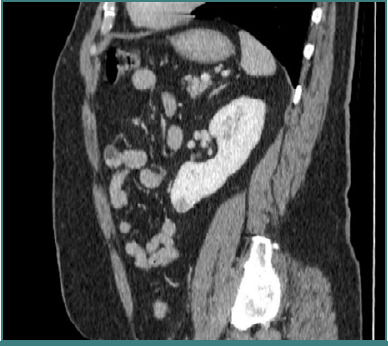

We report the case of a 58-year-old male with metachronous renal tumors and a solitary kidney who had previously undergone an open right radical nephrectomy with extended lymphadenectomy for an invasive renal cell carcinoma (RCC) (pT3a N0M0) in November 2013. In May 2022, during routine surveillance, a left lower pole lesion measuring 2.5 × 2 × 1.6 cm was detected, and the patient was submitted to robot-assisted partial nephrectomy (RAPN). The histopathological study confirmed the presence of a pT1a Fuhrman grade 3 clear cell renal carcinoma. In October 2024, follow-up imaging revealed a new upper pole lesion measuring 4 × 3 × 2.3 cm in the left kidney. The patient was submitted to a novel robot-assisted partial nephrectomy, which was successfully completed using selective clamping of the renal artery. The clamping time was 28 minutes (versus 17 minutes during the initial procedure), and the estimated blood loss increased to approximately 300 mL compared to about 100 mL previously, with a console time of 98 minutes. The patient was discharged after the second surgery in good functional status. The final pathology revealed clear cell RCC, Fuhrman grade 2/nucleolar grade 2 (WHO/ISUP 2016), and pT1a, with negative margins. Despite increased technical challenges during reoperation, postoperative renal function remained stable, underscoring the feasibility of repeat RAPN in a solitary kidney.

Abstract Image